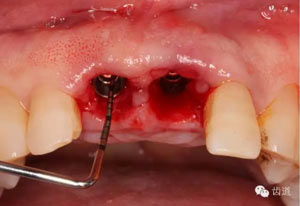

小直徑愈合基臺(tái)就位后唇側(cè)植骨

更換大直徑愈合基臺(tái)

本病例為前牙外傷致根折,牙周無(wú)明顯炎癥,唇側(cè)骨板厚度大于1mm且根方骨量充足,適合即刻種植。術(shù)前簡(jiǎn)易導(dǎo)板的制作以及術(shù)中牙周探針精確的測(cè)量,保證了種植體的三維位置及軸向均按標(biāo)準(zhǔn)的即刻種植手術(shù)進(jìn)行。術(shù)后參考拔除牙齒的頸部形態(tài)制作個(gè)性化愈合基臺(tái),實(shí)現(xiàn)了對(duì)牙齦塑型的早期干預(yù),打破了傳統(tǒng)二期牙齦成型的做法,所成型的牙齦袖口與之前的天然牙相似,有利于維持牙齦形態(tài)的穩(wěn)定和美觀。